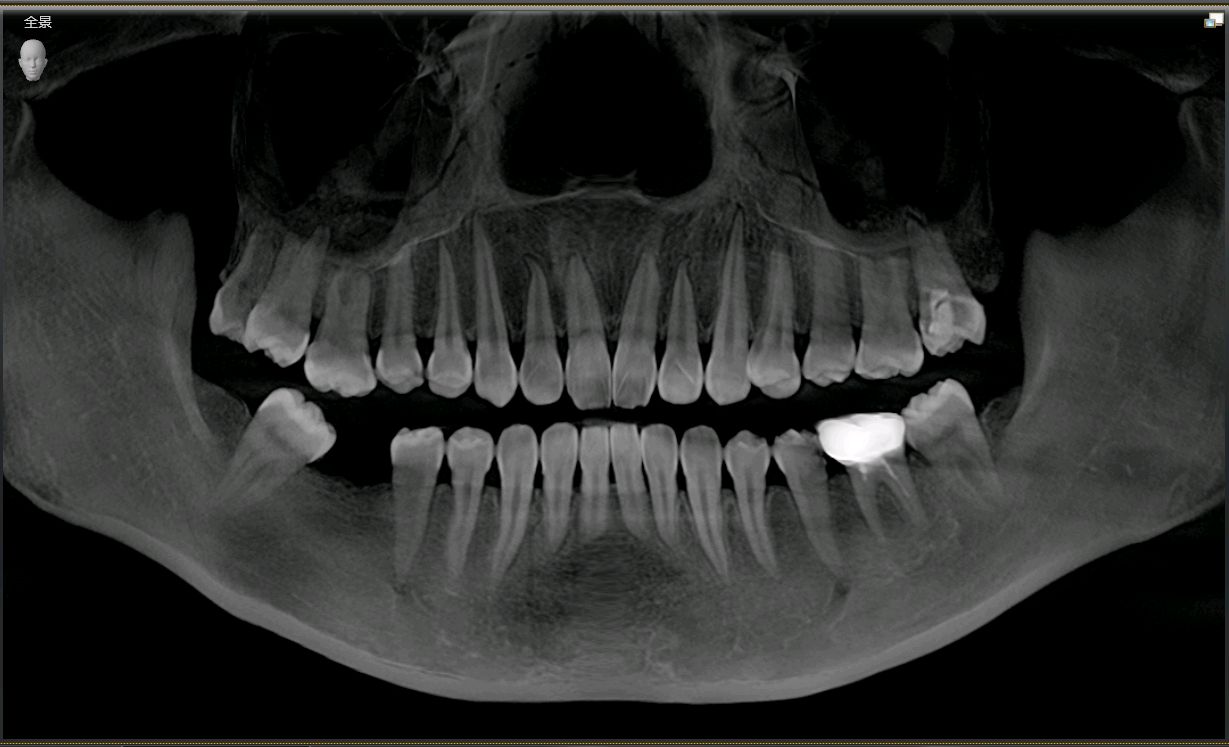

患者女,二十七岁,46牙体缺失近一年,牙槽崎吸收较多,粘膜无红肿、对合牙轻度伸长,邻牙轻微松动,龈周﹣。 x 示牙槽骨密度正常。告知患者治疗方案,患者选择种植修复。抽静脉血20ml,制作 CGF ,植Nobel Pcc 种植体4.3*10mm,上覆盖帽,颊侧骨缺损区植入 bio - oss 骨粉0.25g及 CGF ,盖 bio - Gide 膜及 CGF 膜,严密缝合。直至今日戴牙,咬合适宜,患者满意。